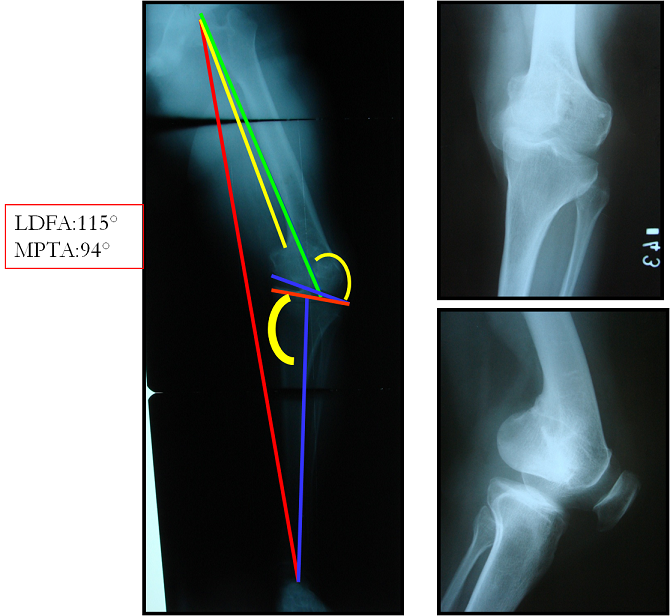

arthritis deformity surgery endoprosthesis hip prosthesis ilizarov ilizarov surgery infected nonunion knee prosthesis lengthening surgery limb lengthening surgery nonunion periprosthetic infection psodoartroz revision surgery total hip prosthesis total knee prosthesis